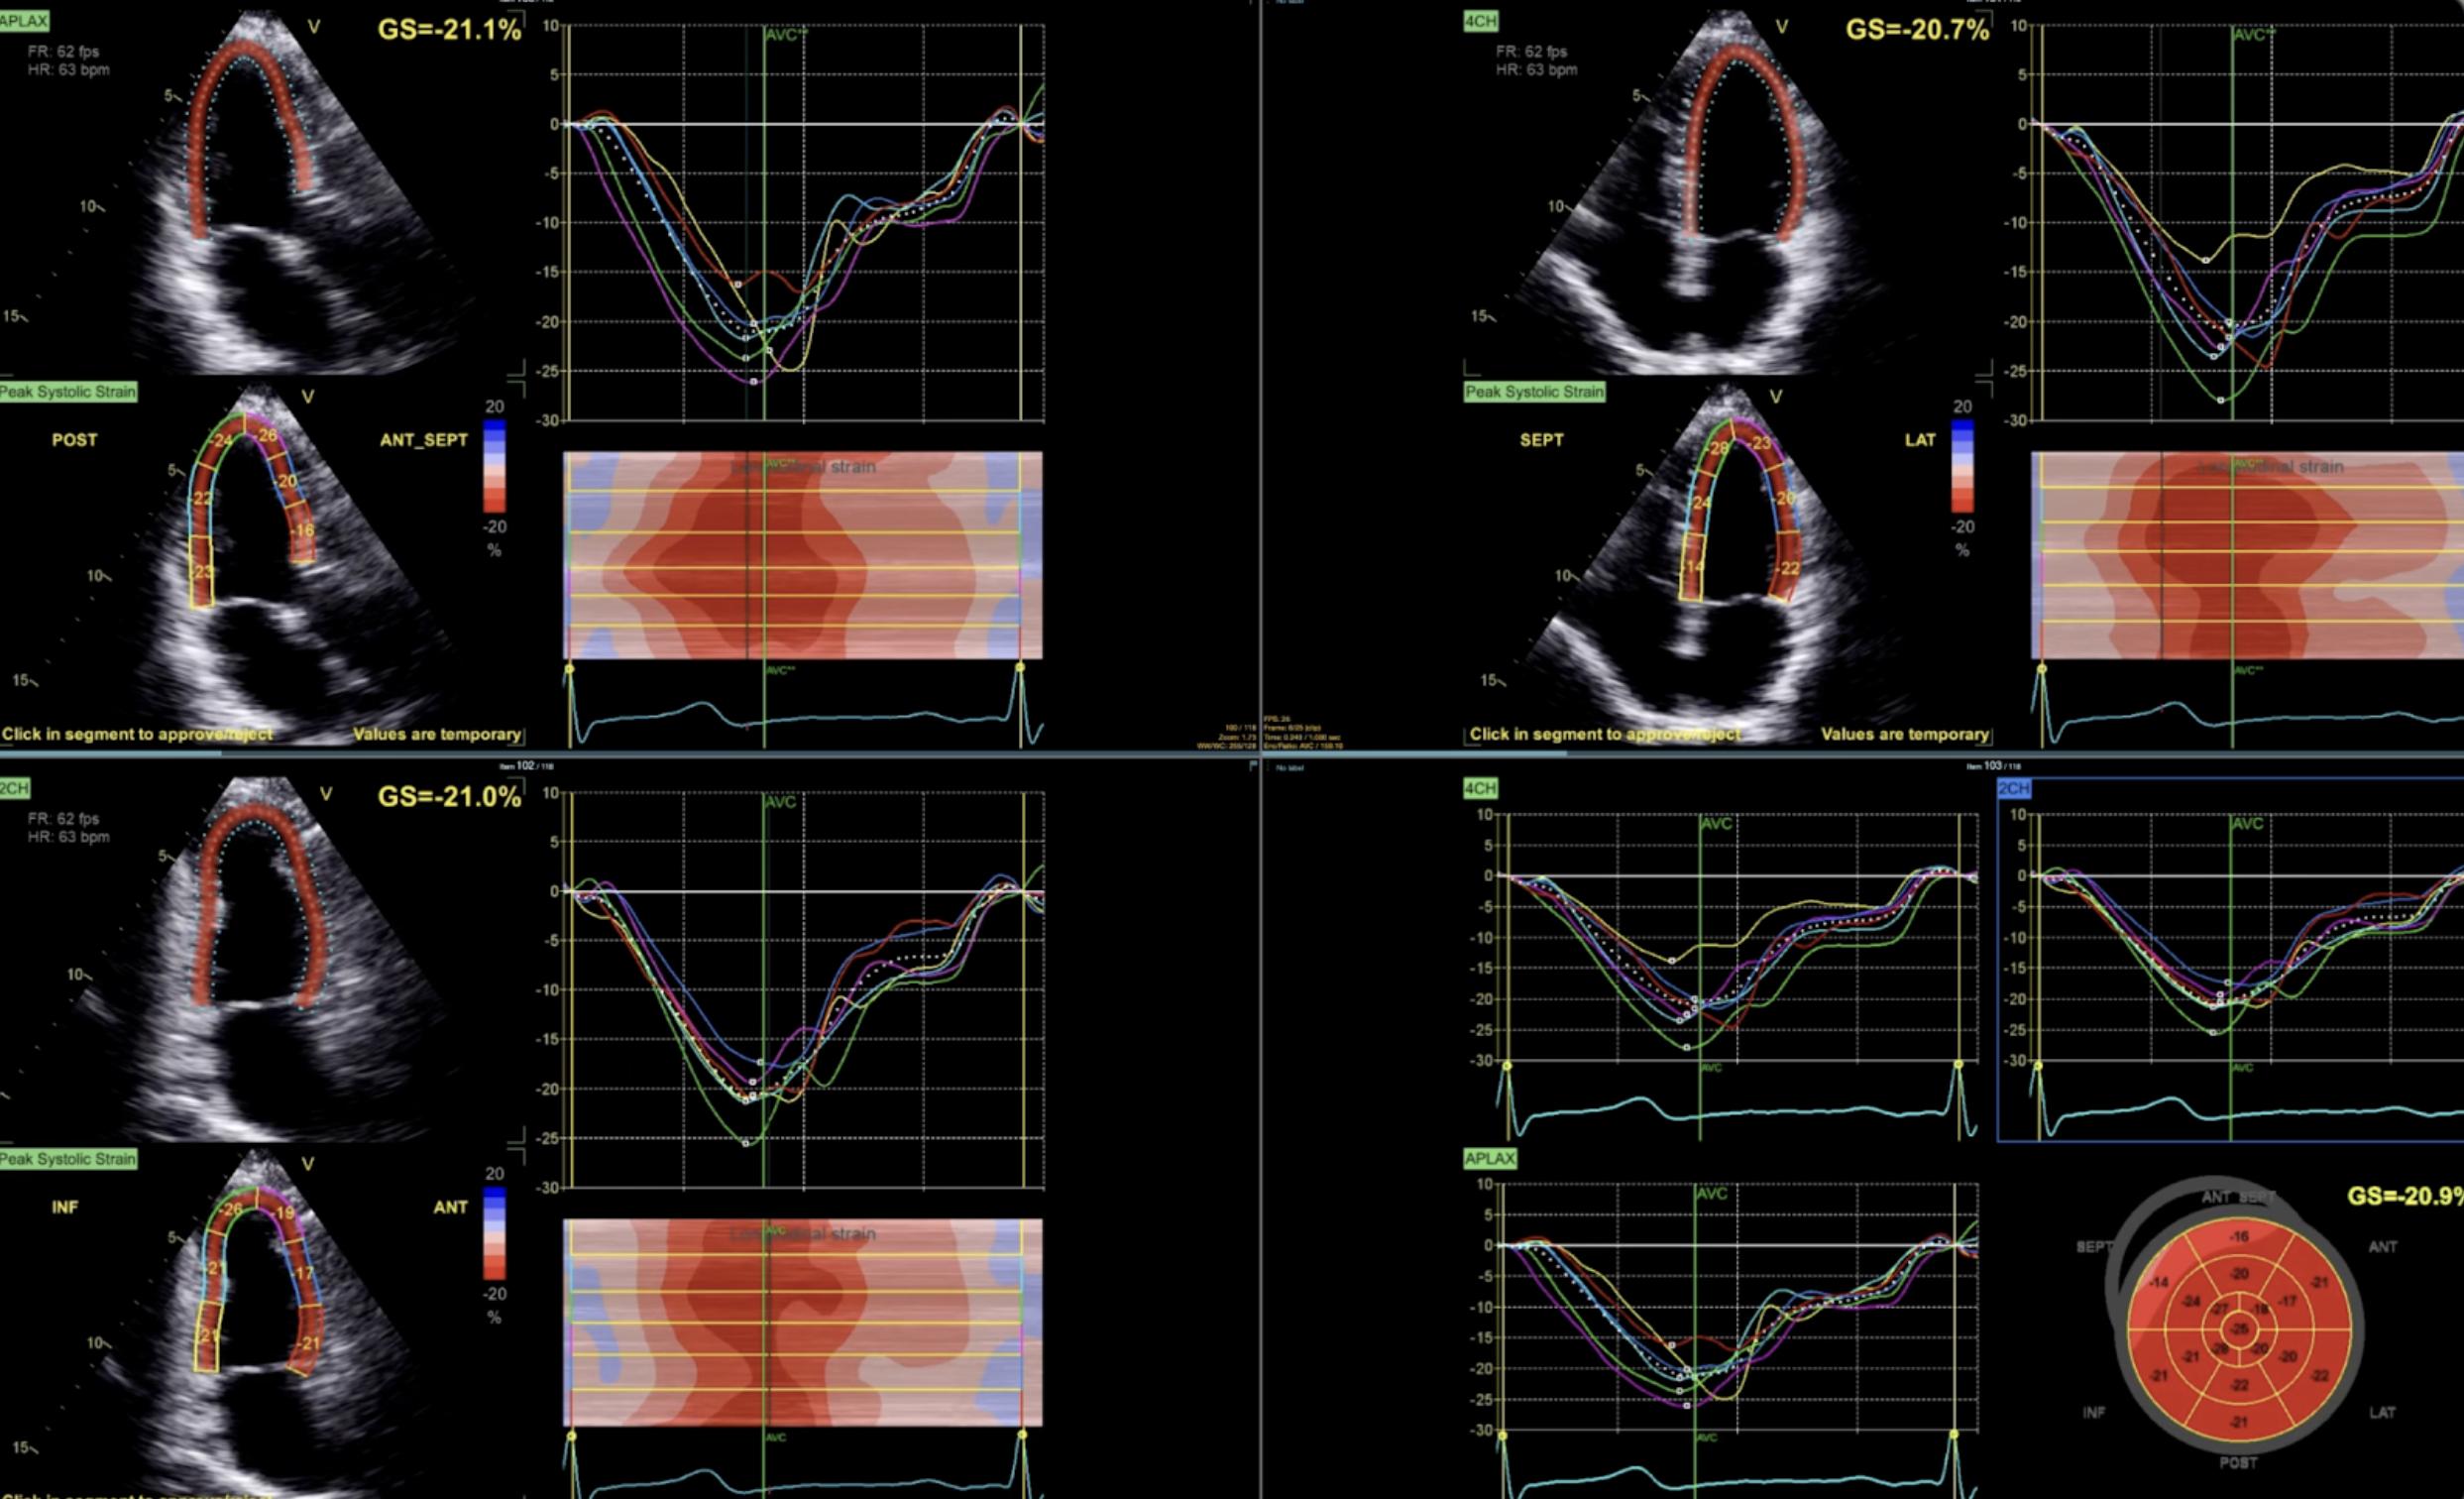

An echocardiogram is an ultrasound of the heart. Using sound waves, it creates real-time images that allow physicians to evaluate the heart's chambers, muscle, valves, and blood flow.

An echocardiogram offers detailed information about how the heart looks and functions. It can show the size of the heart chambers, how strongly the heart muscle pumps, whether the valves open and close properly, and whether there is leakage or narrowing across those valves.

It can also identify enlargement or thickening of the heart muscle, fluid around the heart, elevated pressures on the right side of the heart, and findings that may suggest cardiomyopathy or other structural abnormalities.